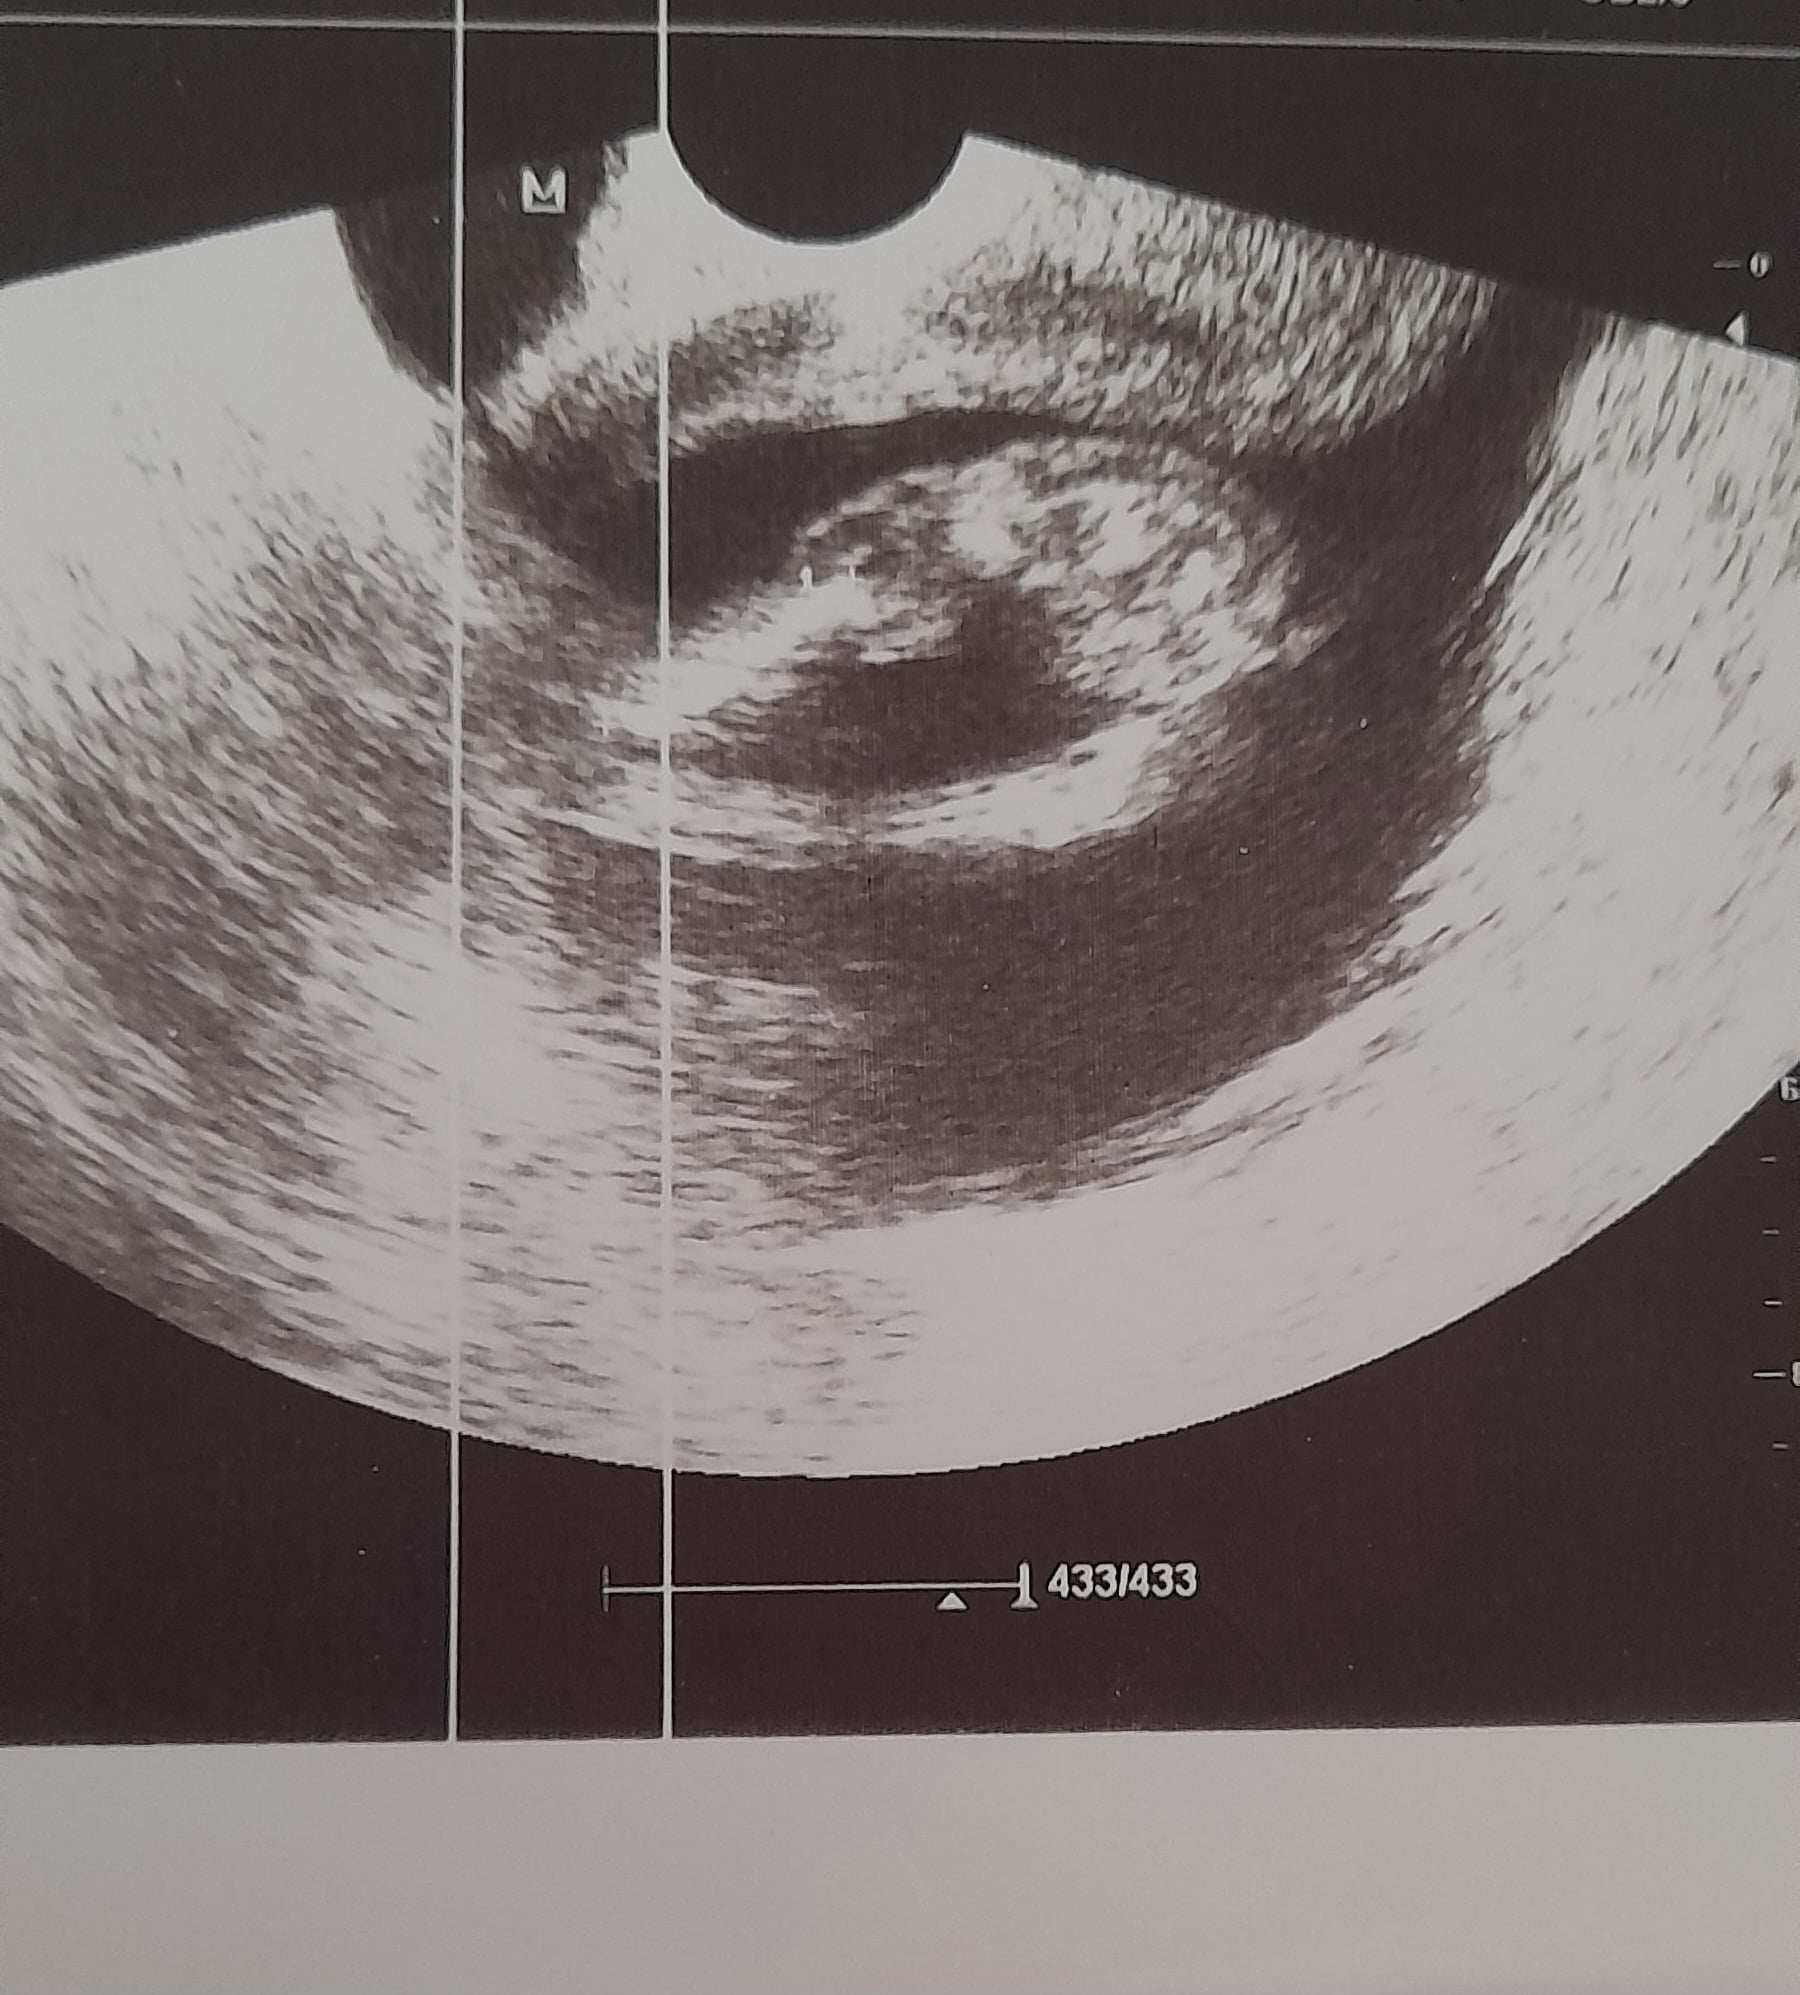

Ben kesenin fotosunu attım gözüküyor mu bilmiyorum sizce cinsiyeti bellimi

Kız gibi duruyor Allah sağlıkla kucağına almayı nasip etsin inşallah ![]()

Kız bu benim tahminim Hayırlı evlat olsun inşallah ![]()

Kız kesesi gibi duruyor sağlıkla gelsin ![]()

Sağlıcakla kucağına al canım. Bence erkek.

erkek gibi, sağlıkla gelsin bebişiniz.